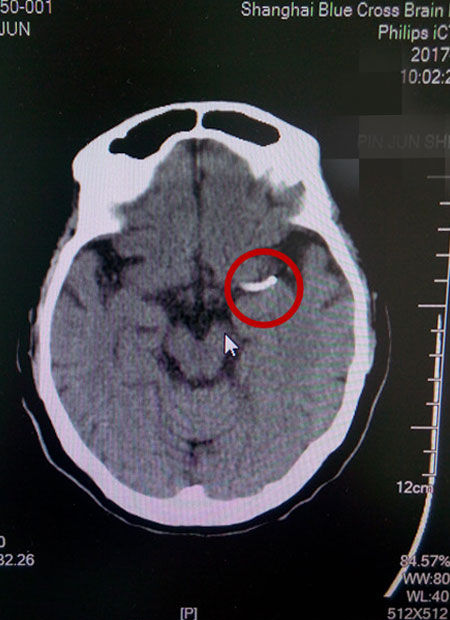

术后CT影像:支架成功置入